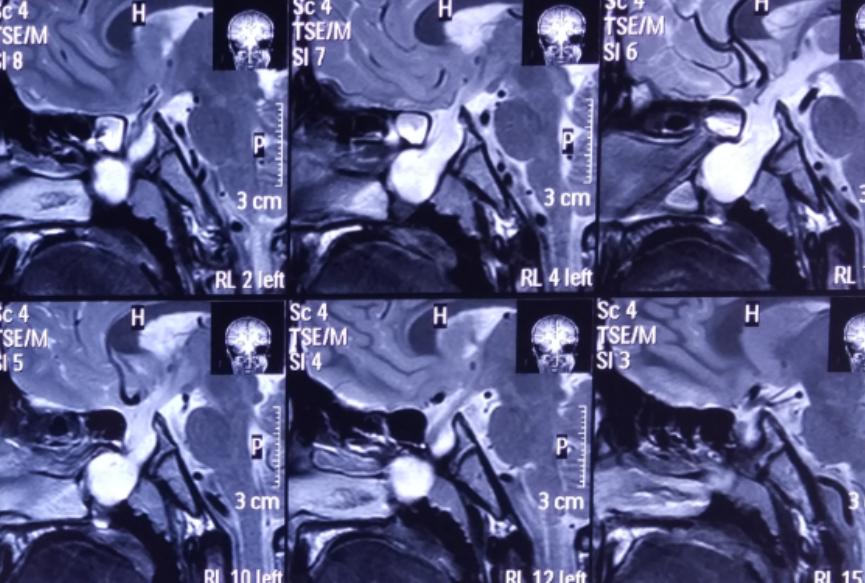

4、患者近期做头颅磁共振提示:鞍区占位性病变;

影像资料